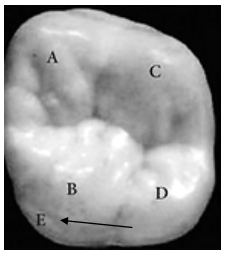

É uma estrutura anatômica situada na face palatina da cúspide mesio-palatina, exclusiva dos primeiros molares superiores permanentes, e corresponde à letra “E” da figura. Assinalar a alternativa que contém a denominação CORRETA.

A

Trabécula molar.

B

Opérculo de molares.

C

Tubérculo de Zuckerkandl.

D

Tubérculo de Carabelli.